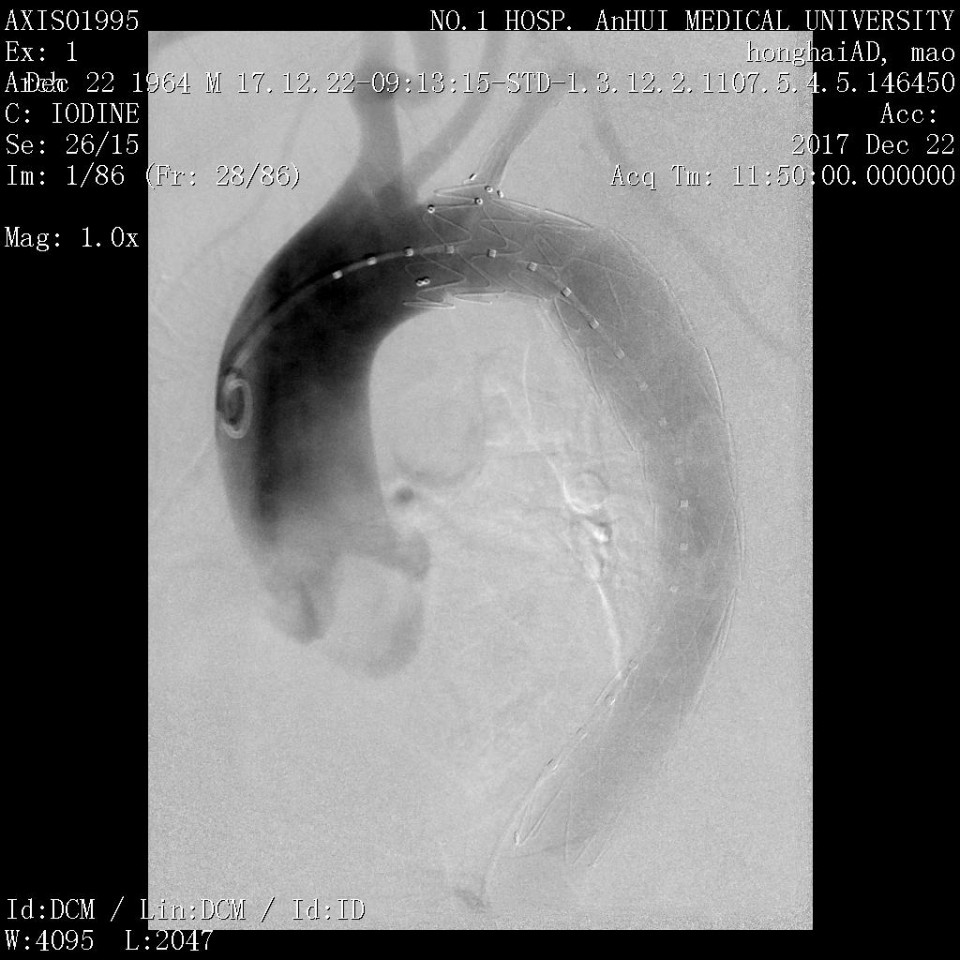

近日,我院血管外科成功应用Castor分支型支架(图1)治疗胸主动脉夹层一例,该病例为我省的首例植入。患者男性,53岁,因“突发胸痛2天”入院,既往有高血压病史。经CTA检查诊断为胸主动脉夹层,破口距离左锁骨下动脉(LSA)36mm,假腔逆撕至左锁LSA(图2、3)。既往一般选用直管型支架,需要部分或全部封闭LSA,但可能增加脑梗和截瘫风险。考虑到患者年龄较轻又是体力劳动者,经科室讨论决定使用Castor一体式分支型覆膜支架,一方面通过增加健康锚定区 (LCCA-LSA距离+LSA直径),进一步降低支架对于血管壁的刺激,从而降低夹层逆撕的风险;另一方面重建LSA保留功能,且不影响LCCA血流。 整个手术过程顺利,最后造影:Castor分支型支架定位精准,无移位;支架近端三重小波段密封性能良好,无内漏,破口被完全封堵,真腔被打开;LSA及LCCA血流通畅,手术圆满成功。病人术后恢复良好(图4、5、6)。